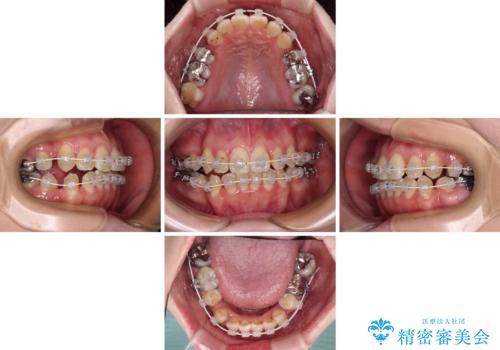

相談の上、表側の目立ちにくいワイヤー装置により矯正治療を継続していくこととしました。

マウスピース(インビザライン)はほとんど使用することができませんでしたが、補助装置により上顎の八重歯は改善しておいたので、ワイヤー装置ではスムーズに治療を終えることができました。